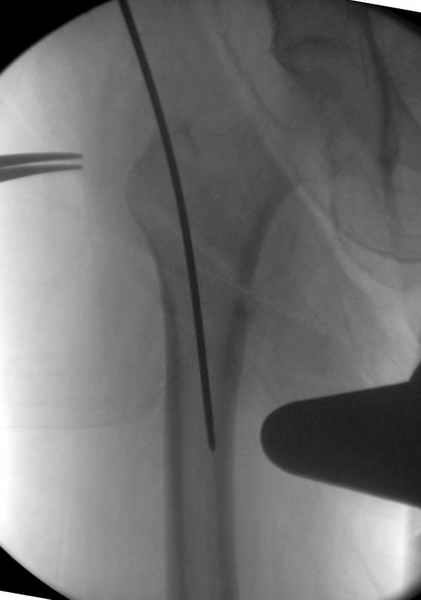

В общем, сделали. См. приложение.

Длина и из-за этого ось получились не совсем такие, как хотелось бы, все-таки срок после той операции уже 6 недель. Может быть, стоило провести дистракцию аппаратом неделю-другую. Заранее спасибо за комментарии и критику.